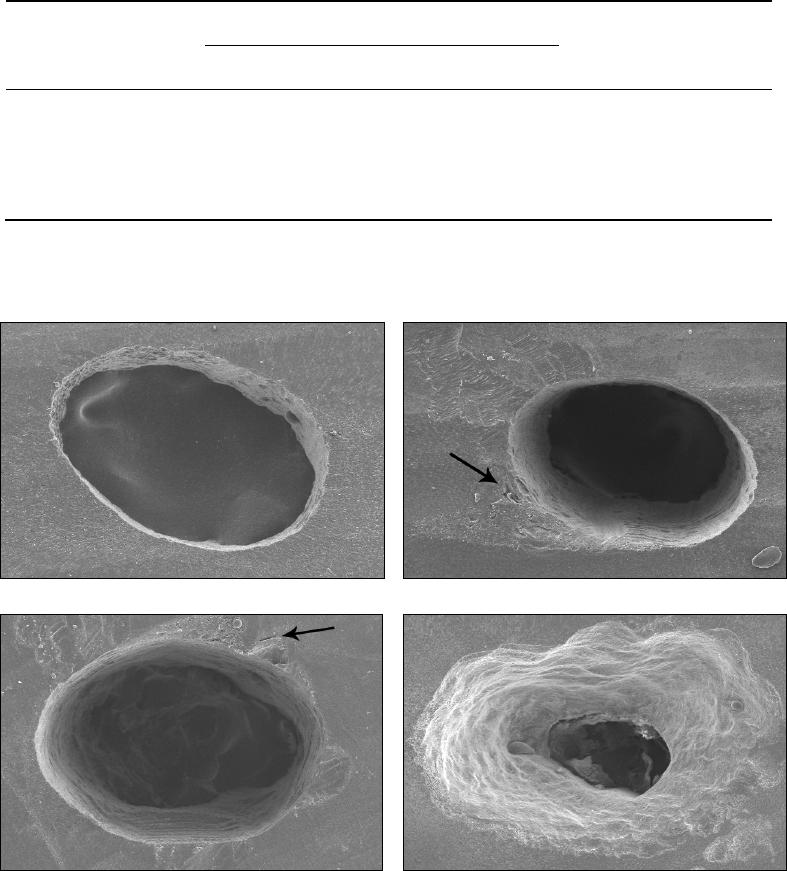

A adaptação da guta-percha com as paredes do canal radicular foi avaliada

de acordo com os escores: 1 – guta-percha bem adaptada às paredes do canal

radicular; 2 – guta-percha recobrindo as bordas das paredes do canal radicular; 3 –

presença de lacunas de até 21,45µm ocasionados pelo deslocamento da obturação

durante a apicectomia; e 4 - presença de lacunas acima de 21,45µm ocasionados

pelo deslocamento da obturação durante a apicectomia (Figura 2). O valor de

21,45µm correspondeu à mediana dos valores encontrados nos espécimes que

apresentavam essas falhas. Todas as mensurações foram realizadas com o auxílio

de um programa de análise de imagens (Image Tool for Windows version 3.00,

UTHSC, SA, USA).